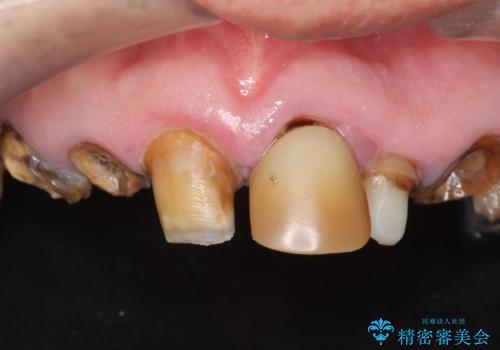

[ジルコニアクラウン] 前歯の見た目を良くしたい

![[ジルコニアクラウン] 前歯の見た目を良くしたいの症例 治療前](https://seimitsushinbi.jp/wp/wp-content/uploads/2021/06/d90ecf81857c5e4b2eee1b8150ea7826-500x350.jpg?v=1623380189)